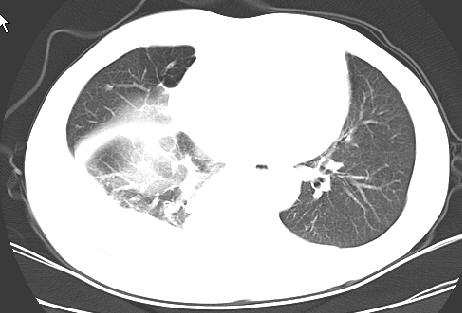

以下是引用草之原在2009-5-2 19:29:00的发言:[br]1.考虑右侧中心型肺ca纵膈淋巴结转移,双侧胸腔积液及右侧叶间裂积液,心包积液。[br]2.两肺上叶病灶,纵膈窗显示部分病灶硬化,考虑:结核。[br][br] [br]

以下是引用ct诊断高手在2009-5-2 19:08:00的发言:[br]我考虑右侧中央型肺癌 伴右肺节段性不张,两肺及纵隔淋巴结转移,右侧胸腔积液。

以下是引用zjzjr在2009-5-2 20:16:00的发言:[br]肺结核,转移瘤.纵隔淋巴结转移或淋巴瘤,右侧包裹性积液、斜裂积液。心包积液。